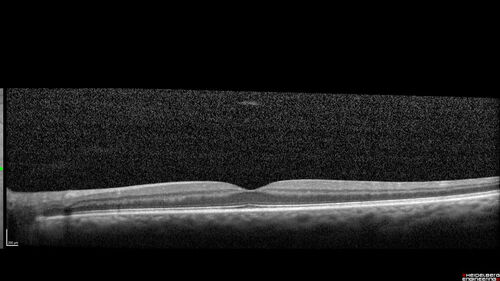

Acute retinal necrosis

67 year old female Hazy vision in the right eye for 5 days.

Medical Hx: TYPE 2 DIAB.. Hypercholesterolemia.

VA 20/40, 20/20

IOP 19, 12

SLE: Trace AC cell OD and moderate vitreous cell OD